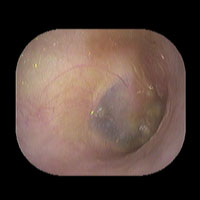

右急性中耳炎(中等症)

鼓膜がやや赤くなっています。鼓膜の奥に膿が透けて見えています。鼓膜の腫れはありません。抗生剤の内服で鼓膜切開を行わずに16日目で治りました。

7日目